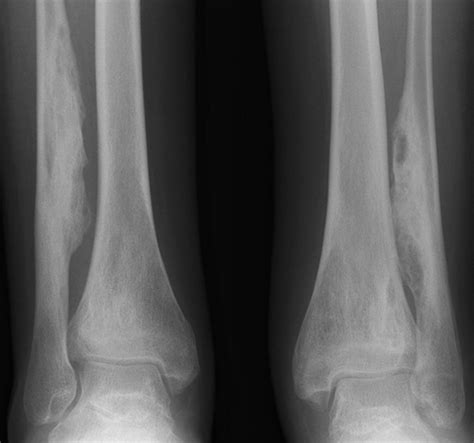

Diagnostic Approach and Imaging

Diagnosing Chronic Multifocal Osteomyelitis is a process of exclusion. Because there is no single laboratory blood test that confirms the diagnosis, physicians rely on a combination of clinical findings, imaging, and, in some cases, a bone biopsy to rule out other more serious conditions like malignancy or bacterial osteomyelitis.

X-rays Useful for evaluating bone damage, though often normal in the early stages.